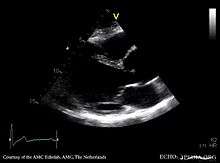

Cardiovascular system

The most serious signs and symptoms associated with Marfan syndrome involve the cardiovascular system: undue fatigue, shortness of breath, heart palpitations, racing heartbeats, or chest pain radiating to the back, shoulder, or arm. Cold arms, hands and feet can also be linked to Marfan syndrome because of inadequate circulation. A heart murmur, abnormal reading on an ECG, or symptoms of angina can indicate further investigation. The signs of regurgitation from prolapse of the mitral or aortic valves (which control the flow of blood through the heart) result from cystic medial degeneration of the valves, which is commonly associated with Marfan syndrome (see mitral valve prolapse, aortic regurgitation). However, the major sign that would lead a doctor to consider an underlying condition is a dilated aorta or an aortic aneurysm. Sometimes, no heart problems are apparent until the weakening of the connective tissue (cystic medial degeneration) in the ascending aorta causes an aortic aneurysm or aortic dissection, a surgical emergency. An aortic dissection is most often fatal and presents with pain radiating down the back, giving a tearing sensation.